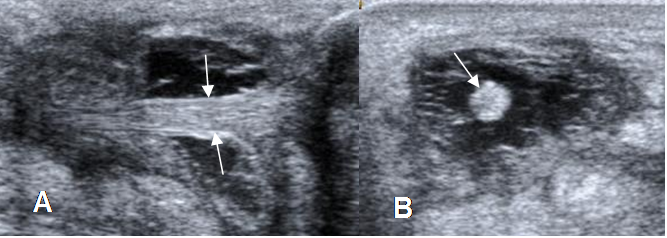

Fig 84. Ruptura parcial del aquiles.

A: Ecografía vista sagital y B: vista axial. Adelgazamiento del tendón por ruptura parcial, el cual está rodeado por líquido.

Fig 85. Ruptura parcial del aquiles.

A: RM axial y B: RM sagital en T2. Adelgazamiento del tendón en la zona crítica, pero conserva la continuidad.